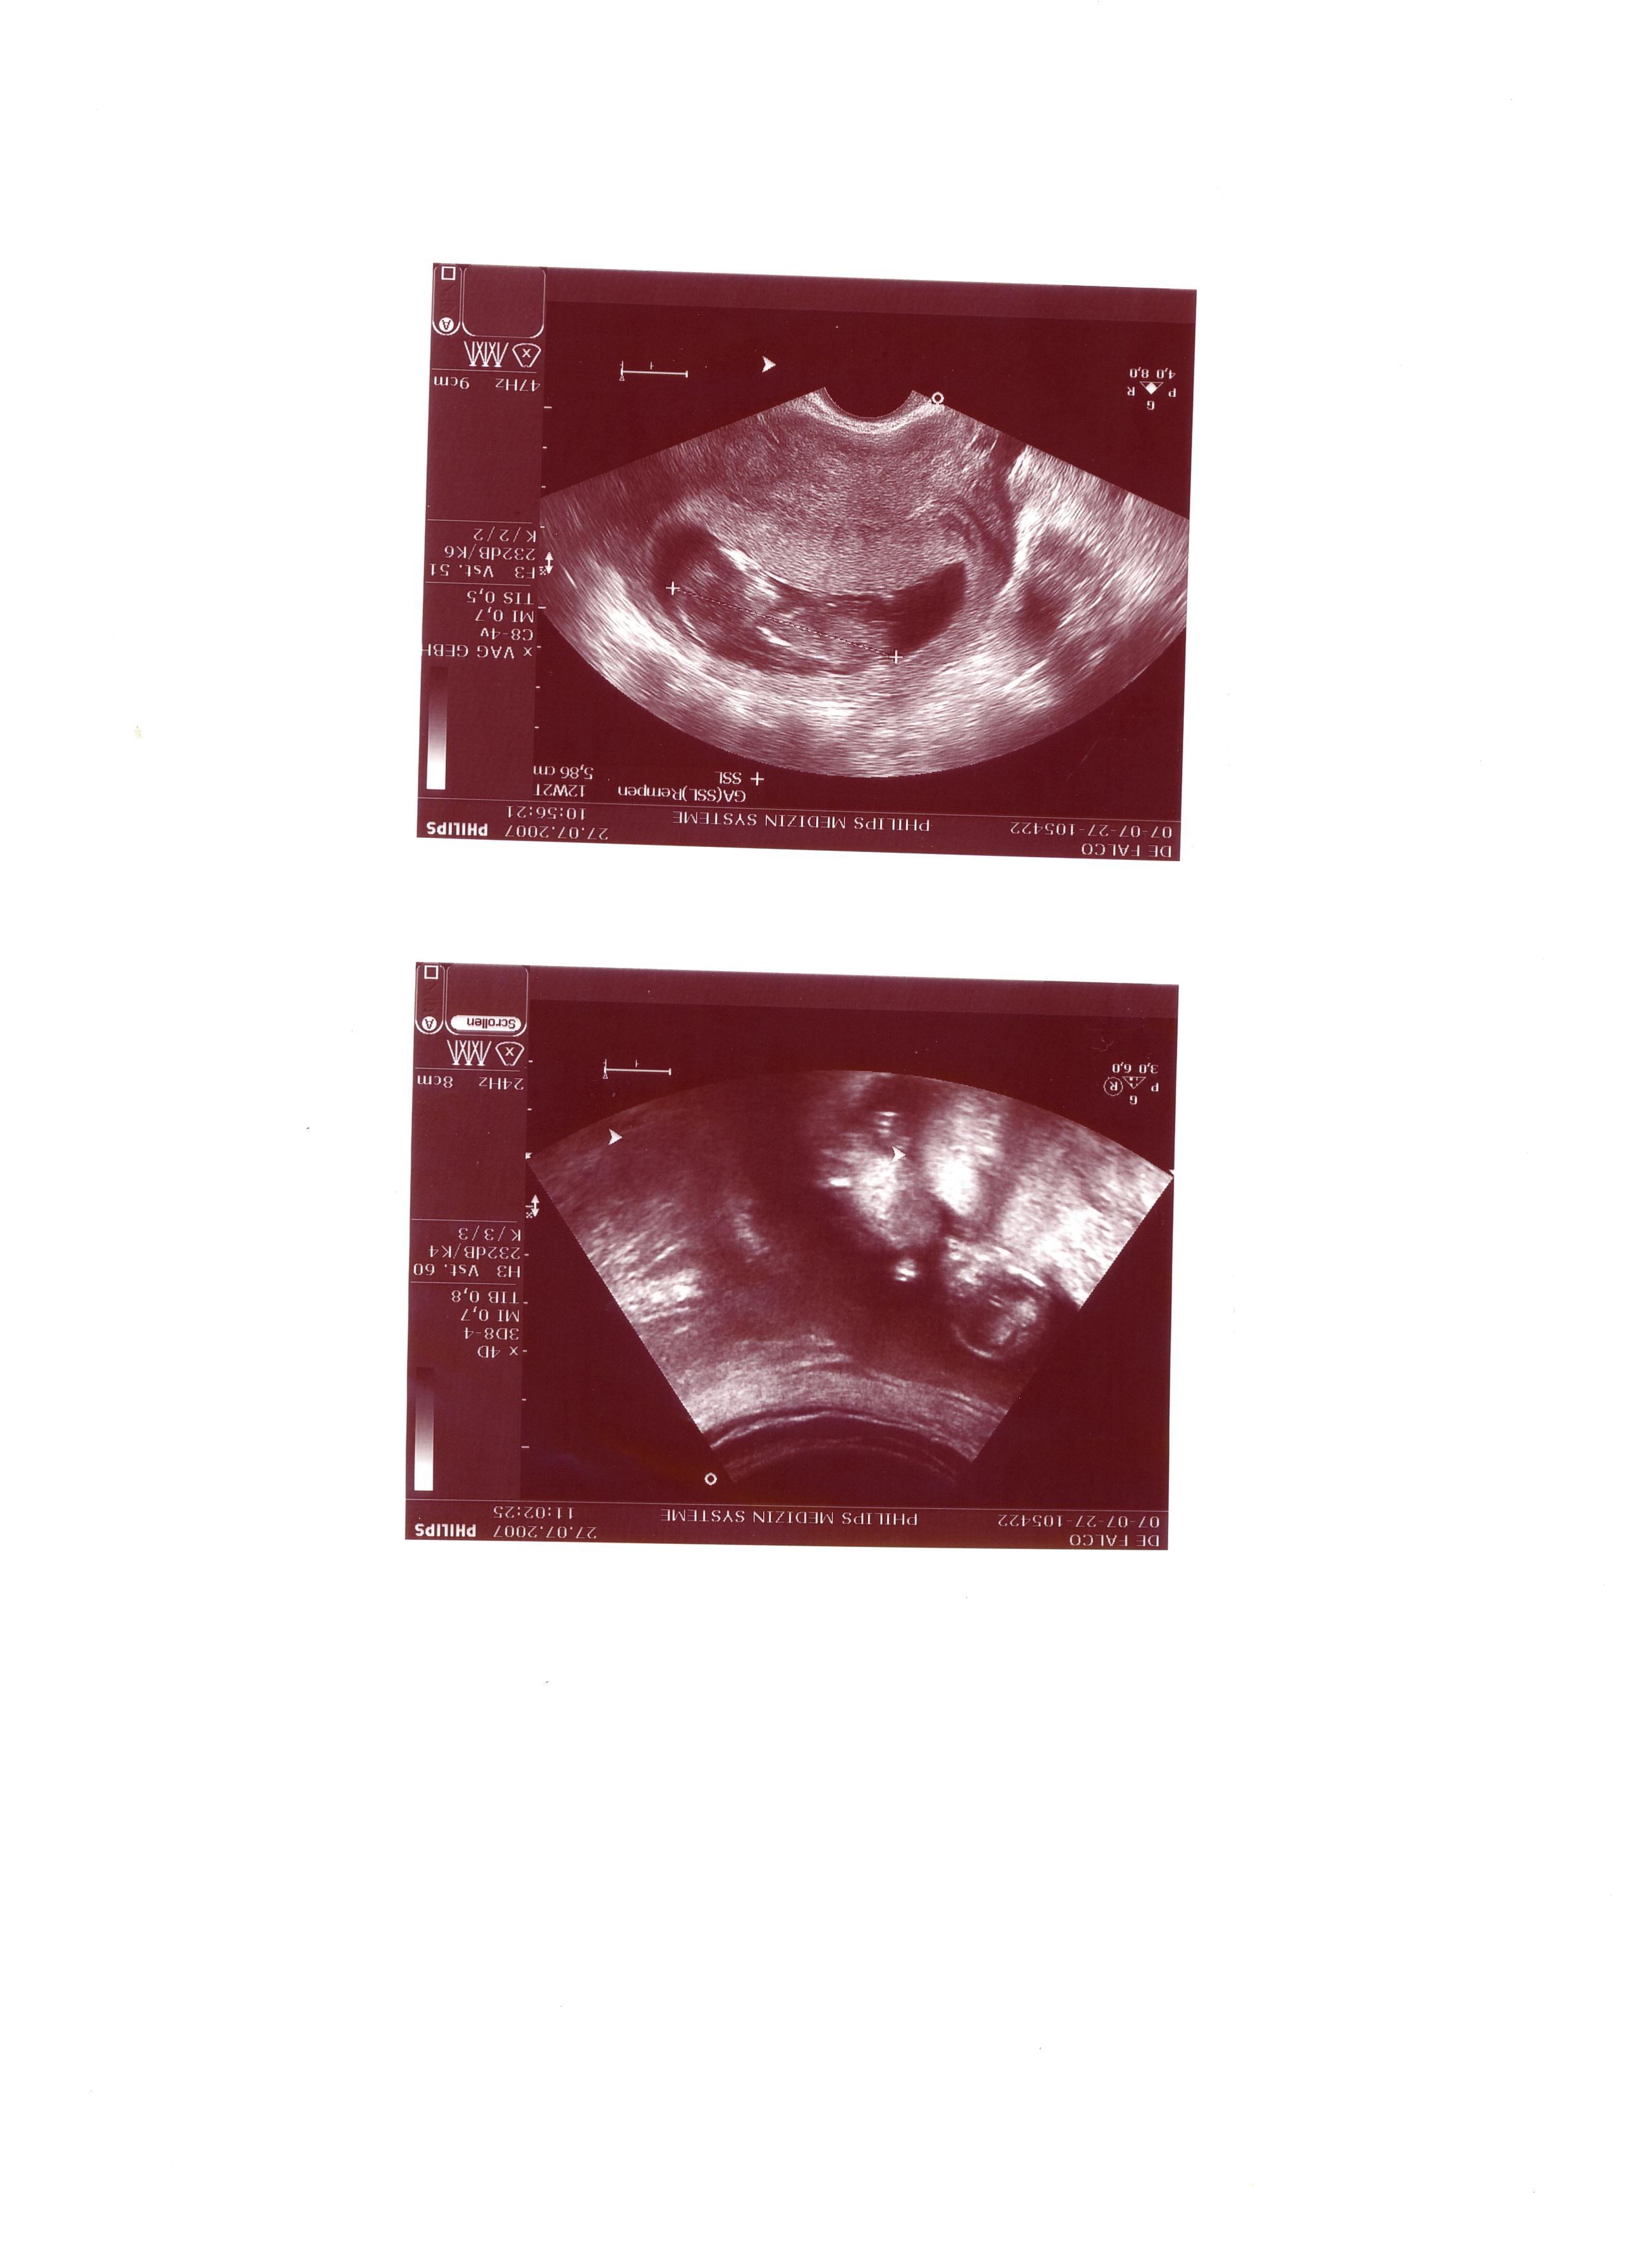

03.07. erster US, eine Fruchthöhle mit Dottersack zu sehen

10.07. das Herzlein schlägt